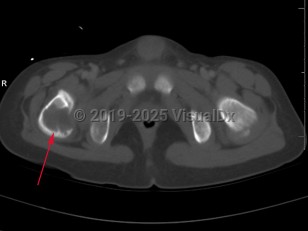

Eosinophilic granuloma of bone in Adult

Langerhans cell histiocytosis (LCH) refers to a spectrum of diseases that includes eosinophilic granuloma (EG), Hand-Schuller-Christian disease, and Letterer-Siwe disease. EG is a rare (seen in 1-5 per million), benign tumor-like disorder that features clonal proliferation of Langerhans cells (antigen-presenting mononuclear cells of dendritic origin) usually found in bones; however, this can involve other organ systems. EG occurs most often in children aged 5-15 years, with a male-to-female ratio of 2:1. EG constitutes 60%-80% of cases of LCH and accounts for less than 1% of all bone tumors. Ninety percent of cases involve a single lesion, usually in the axial skeleton, with just under 10% of cases involving lesions in multiple bones or lesions in other organ systems (ie, skin, pituitary gland, gastrointestinal [GI] tract, lung, spleen, or brain).

The clinical presentation of EG depends largely on the location affected. EG is most often confined to the axial skeleton. EGs are often asymptomatic and found incidentally, or may initially present with pain and swelling of the affected area, with or without decreased range of motion. Commonly affected areas of the skeleton include (in order of frequency): skull, femur, pelvis, mandible, clavicle, ribs, and long bones (of the diaphysis and metaphysis).

Within the spine, EG accounts for 6.5%-25% of all spinal tumors, with the most common location being the thoracic spine, followed by the lumbar and then cervical spine. In cases of EG of the spine, the following symptoms have been reported: neck / back pain, limb weakness, neck / back stiffness with restriction of movements, kyphotic deformity, radiculopathy, and torticollis.